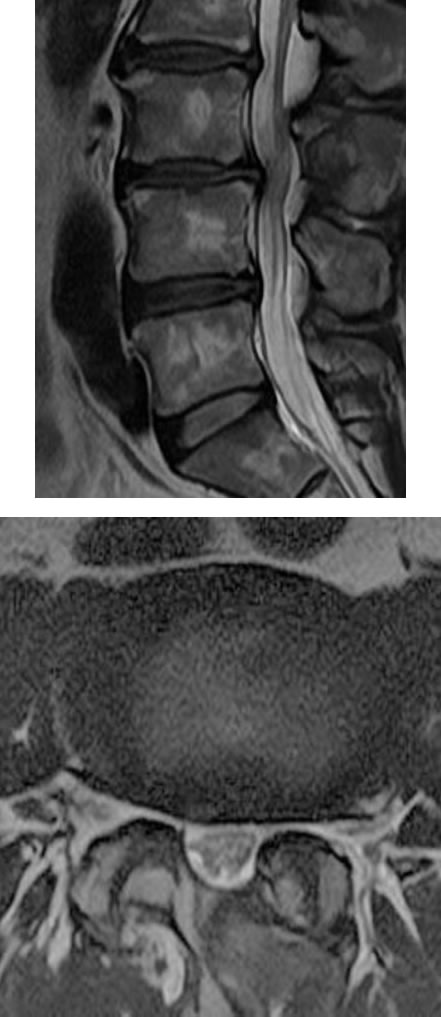

| 腰部脊柱管狭窄症 | |

|---|---|

| 椎間板以外に、靭帯や骨によって神経が圧迫されている状態となります。50歳以上に多いです。 | ![]() (腰椎を輪切りにした図) |